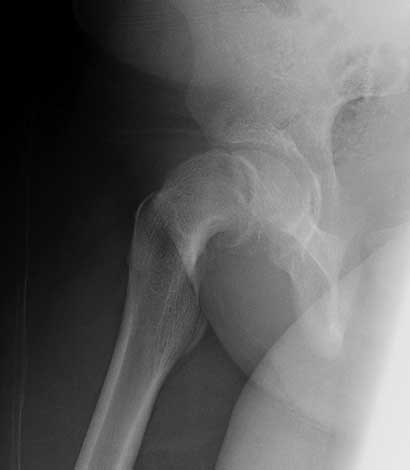

Severe unstable slipped capital femoral epiphysis

Severe unstable slipped capital femoral epiphysis.